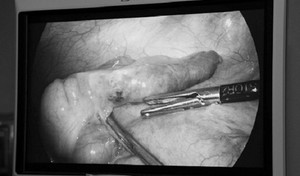

Sau ca phẫu thuật nội mạc tử cung, Bella ngỡ ngàng và tức giận khi các bác sỹ thông báo họ đã tự ý cắt cả ruột thừa của cô dù bộ phận này hoàn toàn khỏe mạnh.